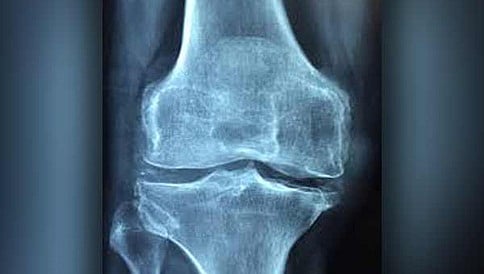

ಆಸ್ಟಿಯೊಪೊರೋಸಿಸ್‌ (ಅಸ್ಥಿರಂಧ್ರತೆ) ಎಂಬ ಮೂಳೆಗಳಿಗೆ ಸಂಬಂಧಿಸಿದ ಸಮಸ್ಯೆಗೆ ಚೀನಾದ ಗಿಡಮೂಲಿಕೆಯಲ್ಲಿ ಮದ್ದು ಇದೆ ಎಂದು ಕೆನಡಾದ ಸಂಶೋಧಕರು ಹೇಳಿದ್ದಾರೆ.

ವಾಷಿಂಗ್ ಟನ್: ಆಸ್ಟಿಯೊಪೊರೋಸಿಸ್‌ (ಅಸ್ಥಿರಂಧ್ರತೆ) ಎಂಬ ಮೂಳೆಗಳಿಗೆ ಸಂಬಂಧಿಸಿದ ಸಮಸ್ಯೆಗೆ ಚೀನಾದ ಗಿಡಮೂಲಿಕೆಯಲ್ಲಿ ಮದ್ದು ಇದೆ ಎಂದು ಕೆನಡಾದ ಸಂಶೋಧಕರು ಹೇಳಿದ್ದಾರೆ.

ಯಾವುದೇ ಅಡ್ಡ ಪರಿಣಾಮಗಳಿಲ್ಲದೇ ಚೀನಾದಲ್ಲಿ ಬಳಕೆಯಾಗುವ ಸಾಂಪ್ರದಾಯಿಕ ಔಷಧ ಆಸ್ಟಿಯೊಪೊರೋಸಿಸ್‌ ಸಮಸ್ಯೆಯನ್ನು ನಿವಾರಿಸುವ ಸಾಮರ್ಥ್ಯ ಹೊಂದಿದೆ. ಅಷ್ಟೇ ಅಲ್ಲದೇ ಮೂಳೆಗಳನ್ನು ಶೇ.35 ರಷ್ಟು ಸದೃಢಗೊಳಿಸಬಲ್ಲದು ಎಂಬುದನ್ನು ಕೆನಡಾದ ಸಂಶೋಧಕರು ಕಂಡುಕೊಂಡಿದ್ದಾರೆ.

ಕೇವಲ ಆಸ್ಟಿಯೊಪೊರೋಸಿಸ್‌ ಅಷ್ಟೇ ಅಲ್ಲದೇ ಸಂಧಿವಾತ ಮತ್ತು ಕೆಲವು ಮೂಳೆಯ ಕ್ಯಾನ್ಸರ್ ಗಳನ್ನೂ ಸಹ ಈ ಗಿಡಮೂಲಿಕೆಯಿಂದ ಗುಣಪಡಿಸಬಹುದಾಗಿದೆ.  ಕ್ಯಾಥೆಪ್ಸಿನ್ ಎಂದು ಕರೆಯಲಾಗುವ ಕಿಣ್ವ (ಎನ್ಝೈಮ್) ನಿಂದ ಉಂಟಾಗುವ ಸಮಸ್ಯೆಗಳನ್ನು ರೆಡ್ ಸೇಜ್ ಗುಣಪಡಿಸಬಲ್ಲದು ಎಂದು ವ್ಯಾಂಕೋವರ್ನಲ್ಲಿ ಬ್ರಿಟೀಷ್ ಕೊಲಂಬಿಯಾ ವಿಶ್ವವಿದ್ಯಾಲಯದ ಸಂಶೋಧಕರು ಹೇಳಿರುವುದು  ಮೂಳೆ ಮತ್ತು ಖನಿಜ ಸಂಶೋಧನೆಗೆ ಸಂಬಂಧಿಸಿದ ಜರ್ನಲ್ ನಲ್ಲಿ ಪ್ರಕಟವಾಗಿದೆ.